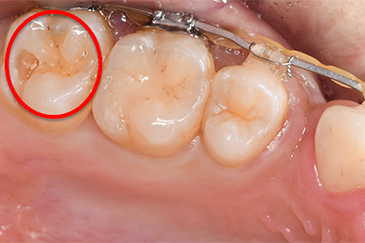

case 3

銀歯の中の虫歯症例

治療前

治療後①

治療後②

基本情報

年齢・性別 40代・女性

主訴 虫歯

左下67

治療内容 左下67

詰め物除去虫歯除去

治療期間 1〜2週間

治療費 3,000円(保険診療)

リスク・副作用 歯を削るときに歯の神経の近くを触っているため、

しみやすくなることや噛んで痛みを感じる事があります。

あまりにもしみる・噛むと痛い場合は神経治療に移行する場合もあります。